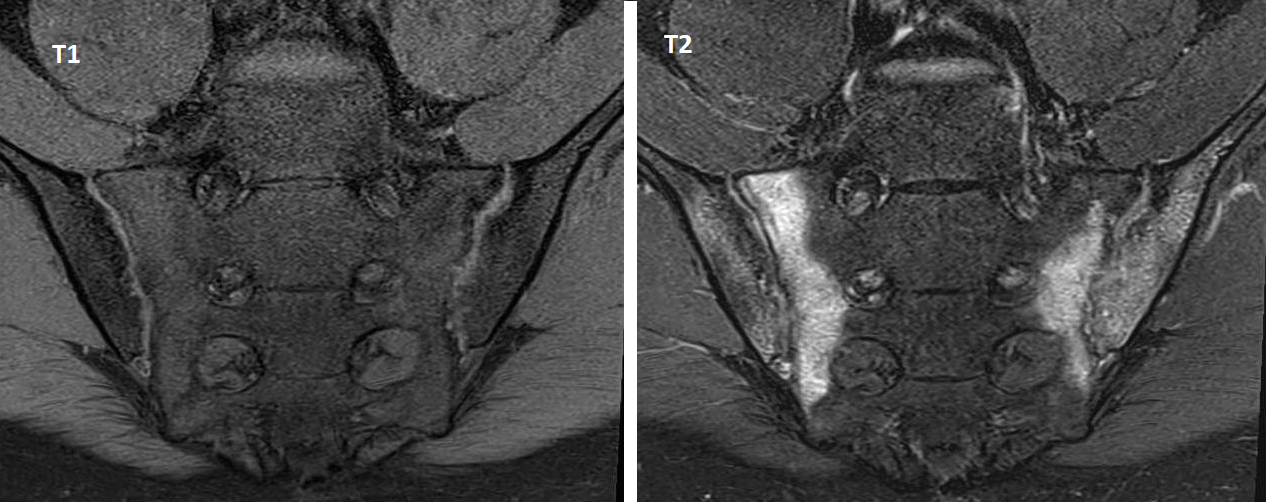

Voici des IRM en séquences T1 et T2 avec suppression du signal de la graisse (Dixon water) :

Figure 1 (Salomé Abdellaoui, La Revue du Praticien)

Oui, sacro-iliite bilatérale.

On observe une sacro-iliite bilatérale avec un hypersignal T2 en regard des deux berges sacro-iliaques.